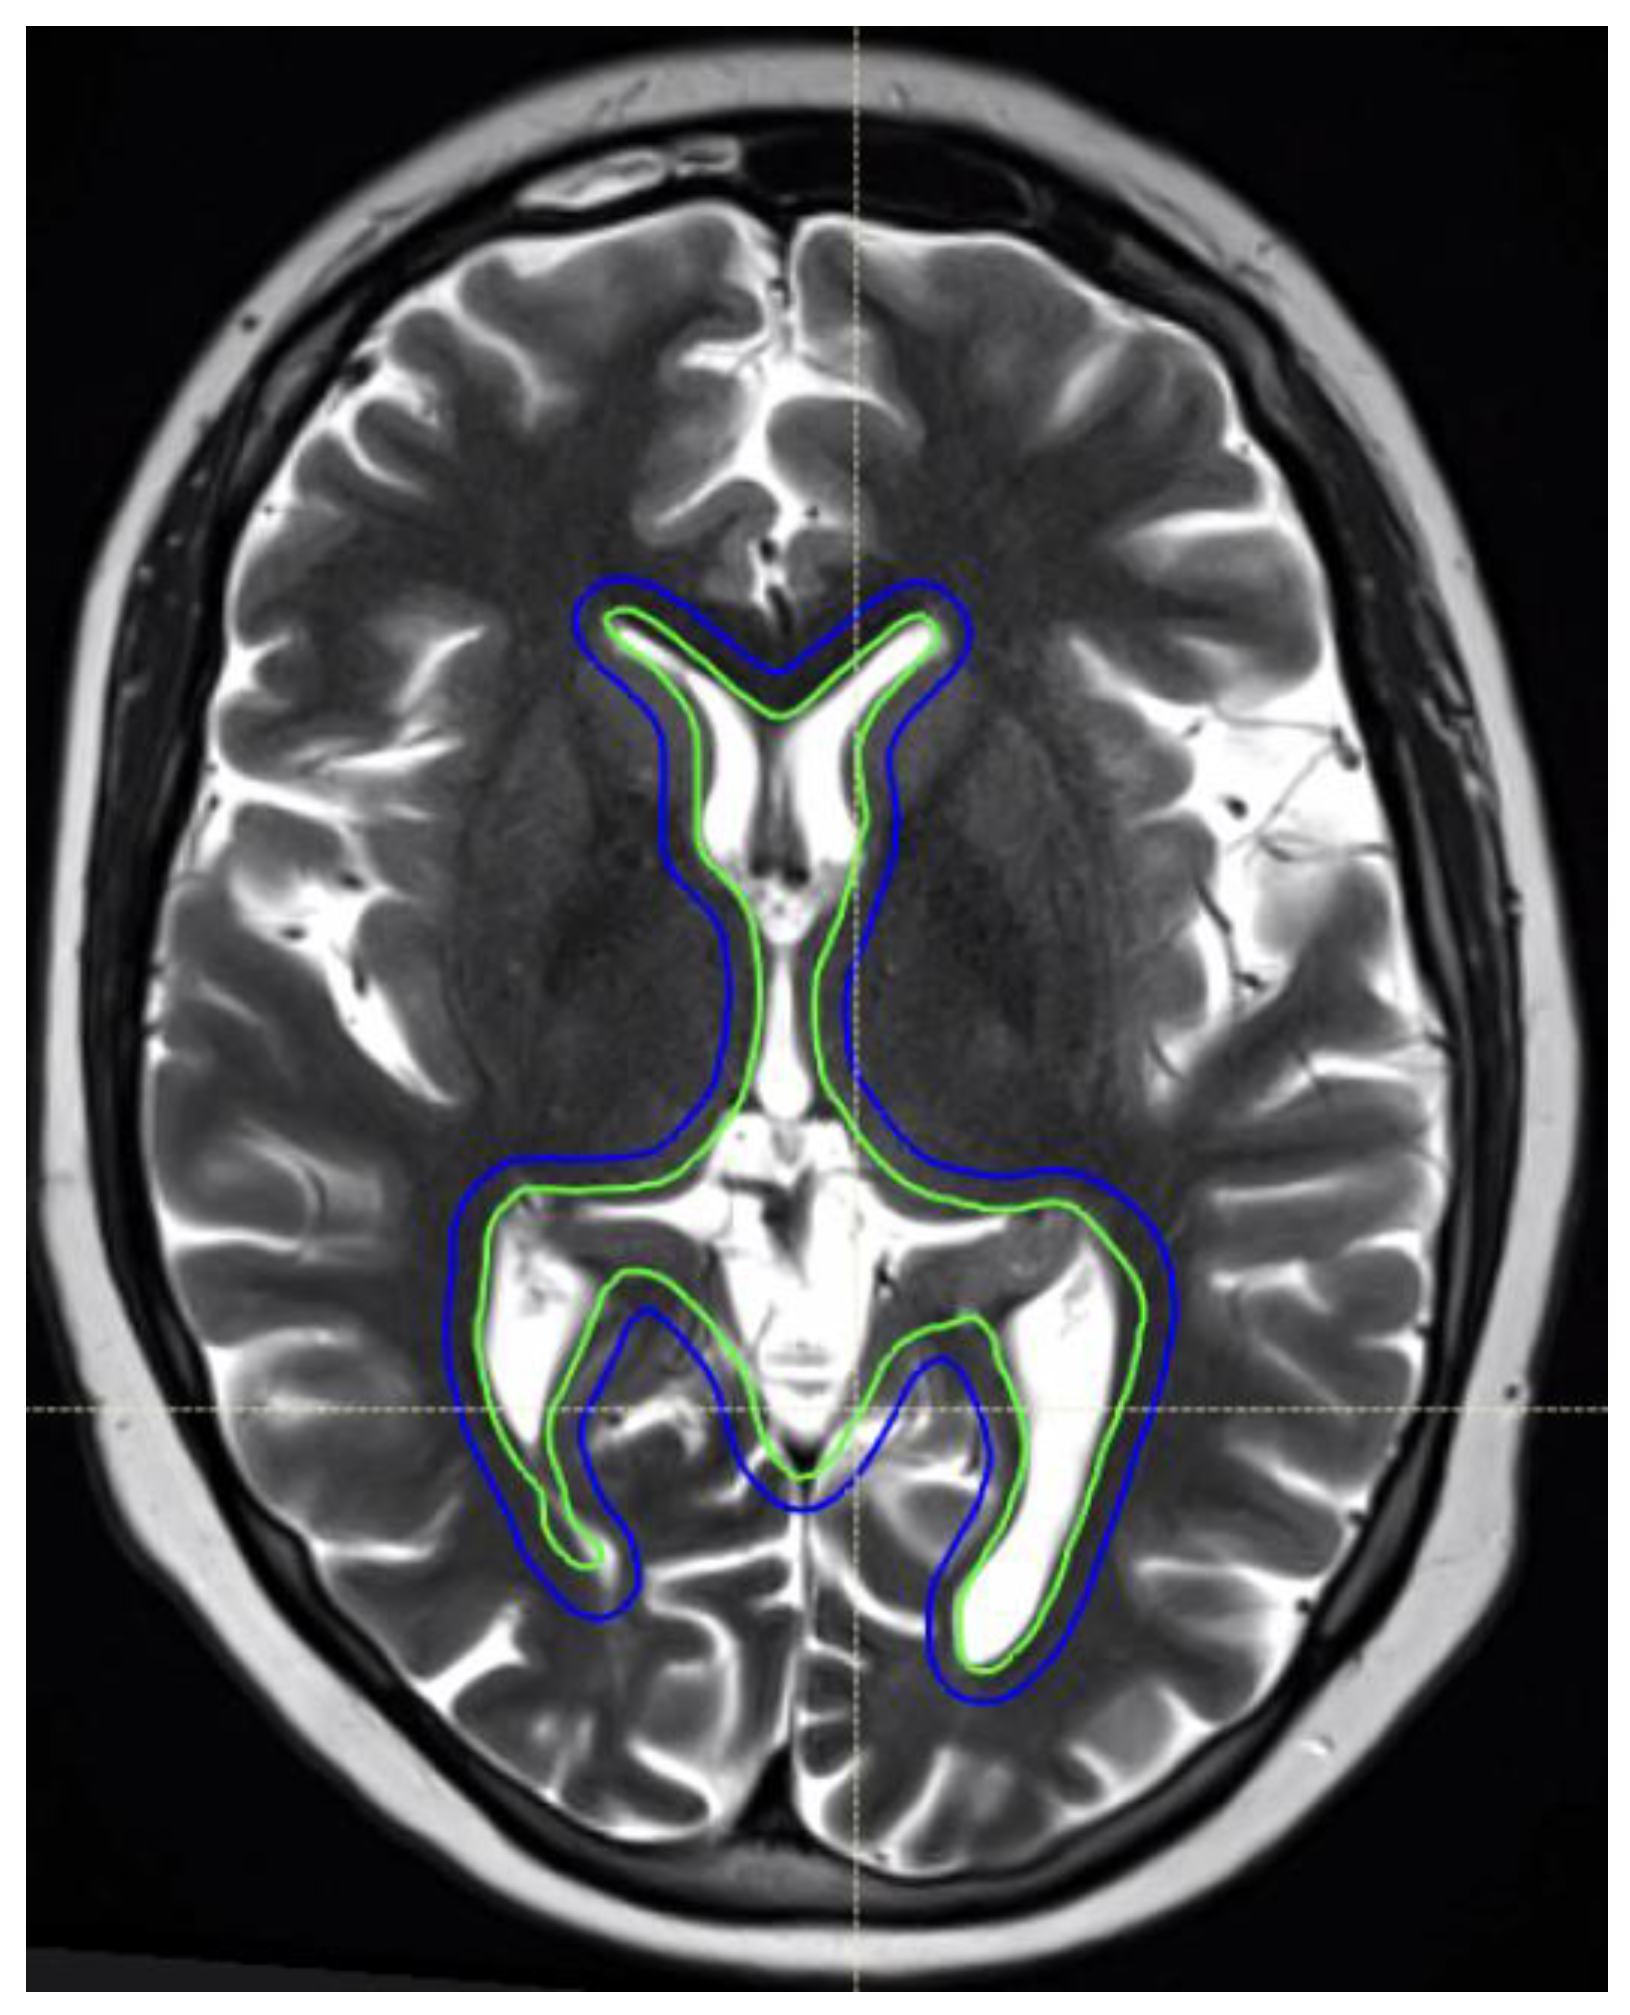

Figure 2.

An 11-year-old female patient with intracranial germinoma. The intracranial RT target volumes are shown as follows: whole ventricular RT CTV (green) and 3 mm PTV geometric expansion (blue).